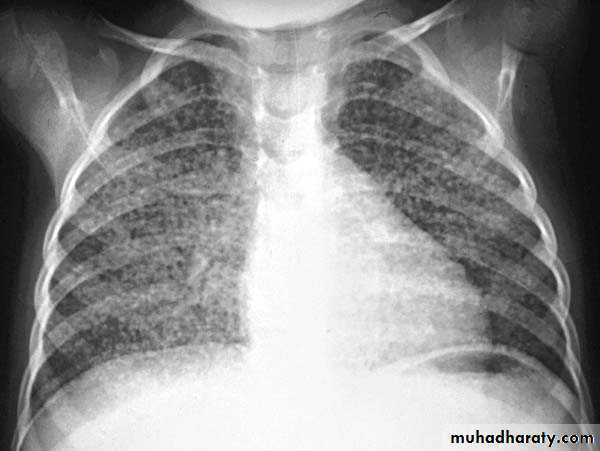

4. Miliary tuberculosis is uncommon but carries a poor prognosis. It represents haematogenous dissemination of an uncontrolled tuberculous infection. It is seen both in primary and post-primary tuberculosis. Although implants are seen throughout the body, the lungs are usually the easiest location to the image. Miliary deposits appear as 1-3 mm diameter nodules . are uniform in size and uniformly distributed